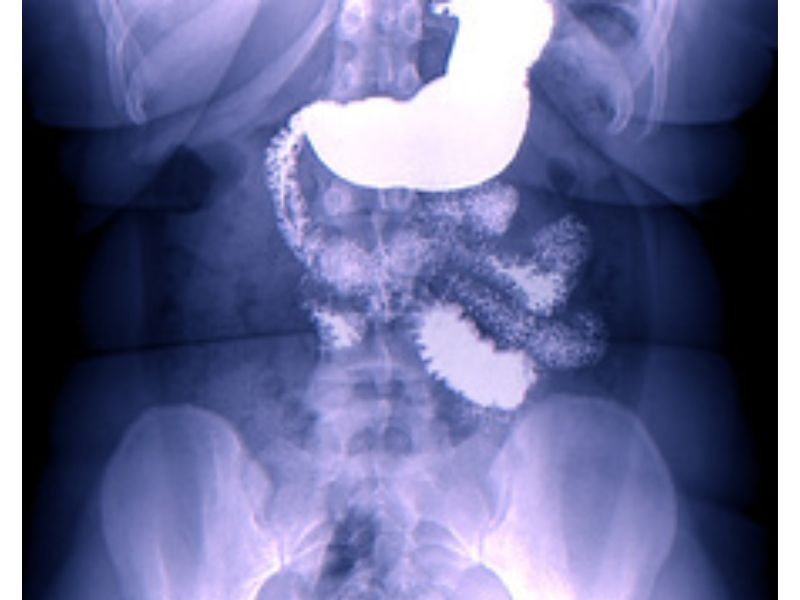

2.4. Chụp X-quang sử dụng chất cản quang Bari

Chụp X-quang sử dụng chất cản quang Bari là phương pháp chẩn đoán hình ảnh giúp quan sát tổng thể cấu trúc và chức năng dạ dày. Phương pháp này thường được sử dụng khi bệnh nhân không thể thực hiện nội soi hoặc cần đánh giá trước khi tiến hành các xét nghiệm chuyên sâu hơn.

Quy trình chụp X-quang:

- Bệnh nhân sẽ uống một loại dung dịch chứa Bari sulfate, một chất cản quang giúp phủ lên bề mặt niêm mạc thực quản, dạ dày và tá tràng.

- Khi Bari bao phủ niêm mạc, bác sĩ sẽ tiến hành chụp X-quang từ nhiều góc độ khác nhau để ghi lại hình ảnh chi tiết của dạ dày.

- Trong một số trường hợp, bác sĩ có thể bơm thêm không khí vào dạ dày để tạo hình ảnh sắc nét hơn, giúp phát hiện những bất thường nhỏ mà chụp X-quang thông thường có thể bỏ sót.

Chụp X-quang sử dụng chất cản quang Bari giúp phát hiện các tình trạng:

- Loét dạ dày, vết sẹo do viêm loét.

- Hẹp lòng dạ dày, hẹp môn vị do khối u hoặc nguyên nhân khác.

- Trào ngược dạ dày – thực quản (GERD).

- Khối u lớn hoặc sự thay đổi hình dạng dạ dày do ung thư giai đoạn tiến triển.

Phương pháp này thường áp dụng trong các trường hợp:

- Bệnh nhân không thể thực hiện nội soi do chống chỉ định hoặc quá lo sợ thủ thuật.

- Cần đánh giá chức năng tiêu hóa, chẳng hạn như trào ngược dạ dày thực quản hoặc nghi ngờ hẹp môn vị.

- Kiểm tra sơ bộ trước khi thực hiện các xét nghiệm chuyên sâu hơn như nội soi hoặc chụp CT dạ dày.

Mặc dù có thể phát hiện những bất thường trên bề mặt niêm mạc dạ dày, nhưng phương pháp này không thể phát hiện tổn thương ở lớp sâu của dạ dày hoặc ung thư giai đoạn sớm.